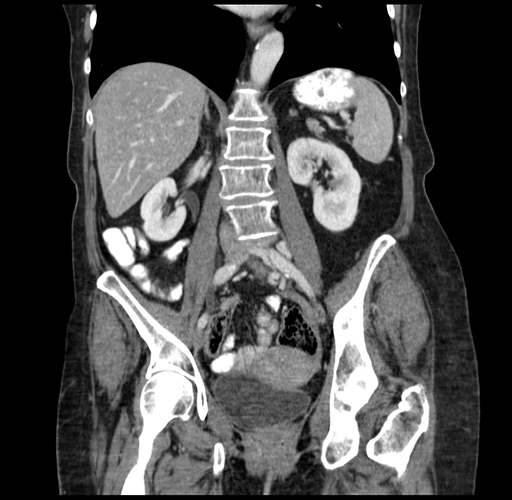

Pre-Chemo: Coronal Venous

Coronal Venous